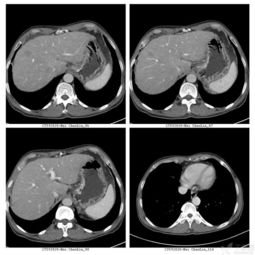

这个问题对你来说可能有点专业。淋巴结比如说原来ct值是23hu,增强扫描时ct值达到了33hu,这个就算是轻度强化了。

从形态上来看,虽然长径都达到了1公分,但是短径都只是长径一半,说明还是良性的“瘦”型淋巴结。加上边界清楚,可以排除恶性病变。

延迟扫描增强消退,仍表现为低密度。少数出现“牛眼征”,即病灶中心为低密度,而边缘强化呈高密度。外周又有一层稍低于肝密度的水肿带。可侵犯局部血管,病灶边缘也少见假包膜。

均匀强化,可能是炎症。可以吃1-2周消炎药后,复查B超。必要时可以切除淋巴结送病理,证实是炎症还是转移。